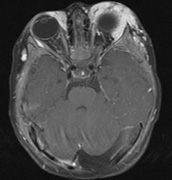

Fig. 15. Tuberous Sclerosis Complex. (a) Patient 1: Axial CT scans demonstrating typical calcification of subependymal nodules in a 13-year-old girl with a history of seizures. (b and c) Patient 2. (b) Axial T2-weighted images demonstrate calcified subependymal nodules (arrowheads) and cortical tubers typical of tuberous sclerosis. (c) Widespread cortical tubers are seen on a coronal FLAIR sequence as thickening of the cortex and high signal of the subcortical white matter.